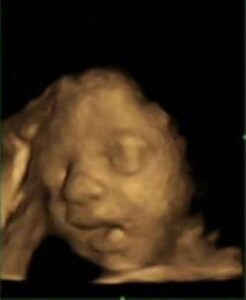

La scoperta è di ricercatori dell'Università Sapienza di Roma ed è stata anticipata da "Radiology". Il coordinatore Lenzi: "La diagnosi...

Meno invasivo e con meno errori Non solo è meno invasivo, ma può essere eseguito in anticipo e produce un...

E' un maschio o e' una femmina? La consueta domanda posta dai neo-genitori alla prima ecografia effettuata dal medico durante...